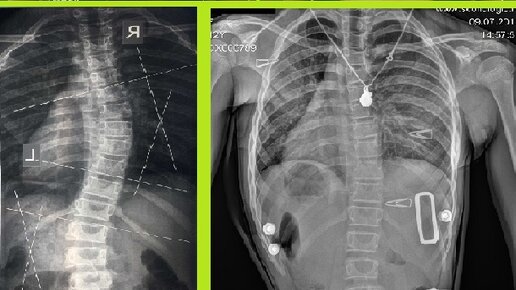

Корсет Шено используется для консервативного лечения идиопатического подросткового сколиоза. Его основная задача - остановить прогрессирование сколиоза и улучшить эстетические вид. Эффективность корсетирования уже не является спорным вопросом и на сегодняшний день есть 2 четко определенных фактора, связанных с положительными результатами и успехом корсетирования: 1 - коррекция угла Кобба в корсете; 2 - комплаентность - выполнение строгих рекомендаций врача, замотивированность в лечении. Нам часто...